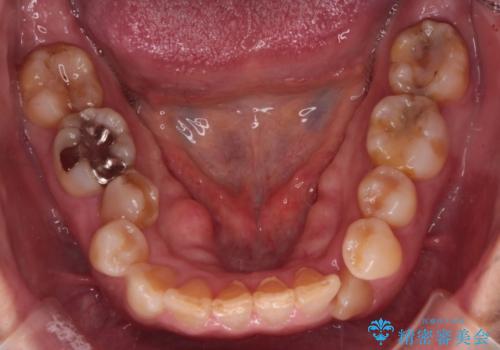

インビザラインで非抜歯矯正|ゴムかけで下顎犬歯の低位を改善し、噛み合わせも最適化

- 患者様は、下顎の犬歯が通常より低い位置にあり、噛み合わせのバランスが崩れていることを気にされて来院されました。診査の結果、抜歯せずに歯をきれいに並べるスペースを確保しながら、**ゴムかけ(顎間ゴム)**を使用して下顎犬歯の高さを適正に調整する方針を立てました。併せて、奥歯の噛み合わせも改善し、全体のバランスを整えることを目標としました。

治療はインビザライン(マウスピース矯正)を使用し、歯列全体を計画的に移動させながら、下顎犬歯の低位をゴムかけによって徐々に引き上げました。患者様にはゴムの装着をしっかり継続していただき、順調に改善が進行。最終的に奥歯の噛み合わせも安定し、全体の咬合バランスが整いました。治療後は「自然な噛み心地になり、見た目も満足」と患者様にも喜んでいただきました。